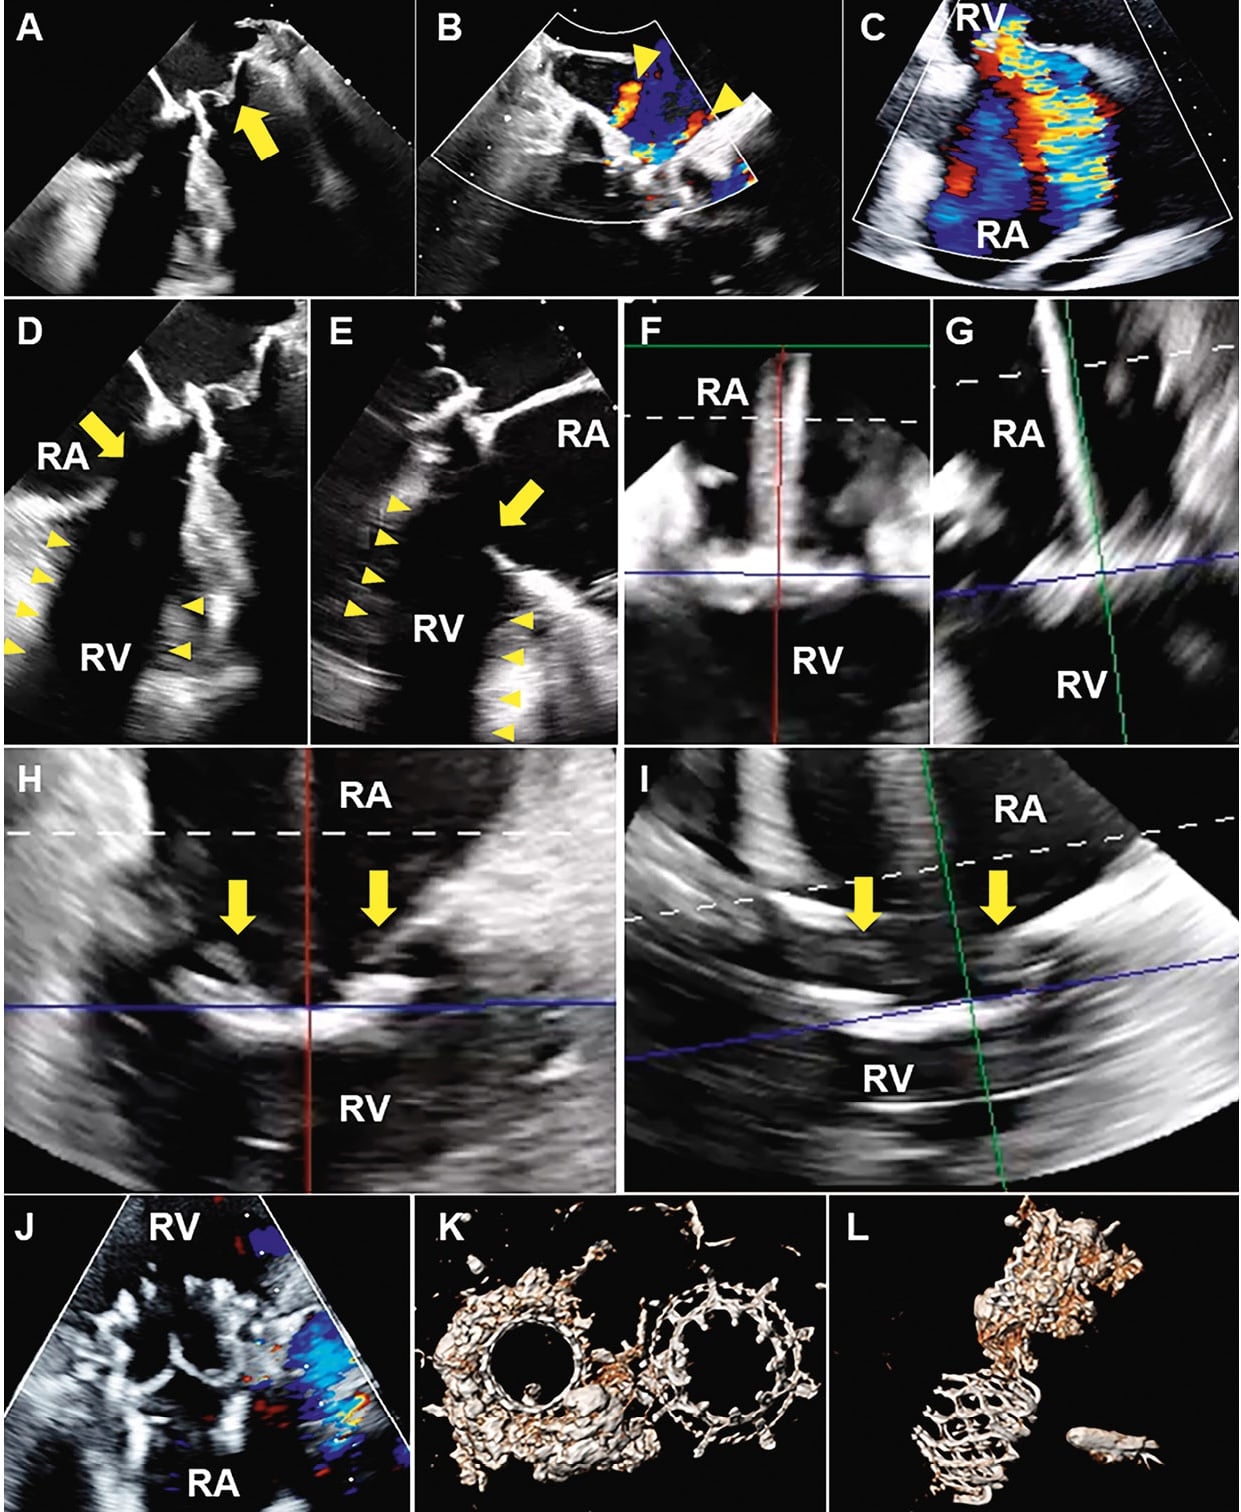

A 73-year-old female with a history of rheumatic fever and severe mitral stenosis who had undergone TMVR presented with severe tricuspid regurgitation. 3D ICE-guided TTVR was performed, with a successful outcome.